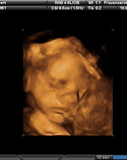

Julian Löbbert

* 09.05.2013 in Hamm

† 09.05.2013